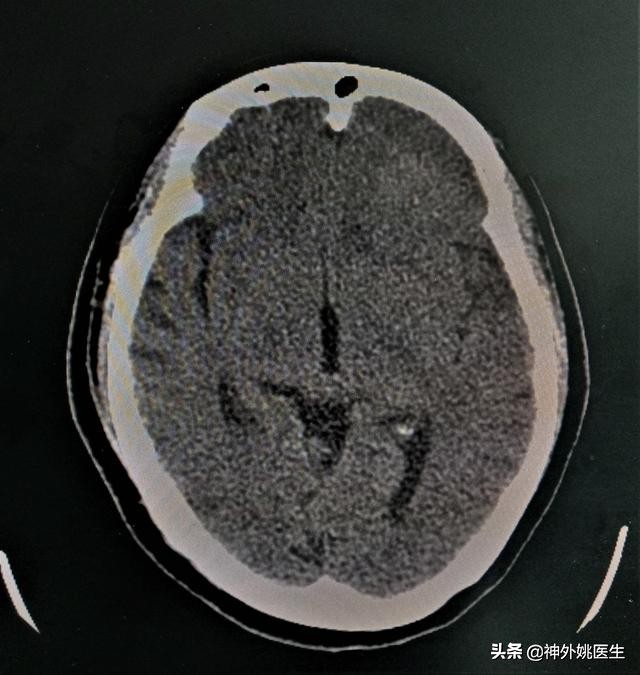

头CT检查:左额部占位,考虑脑膜瘤。(图1、2)

图1 左额部可见类圆形等密度影,大小约3.6cm x 3.9cm。

图2 左前颅底骨质凹凸不平,未见骨质明显破坏。